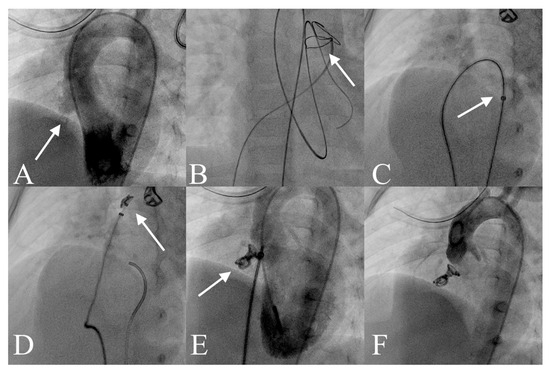

Evaluation of the Safety and Efficacy of Transcatheter Closure of Perimembranous Ventricular Septal Defects with a Single Device Type: A Single-Centre Experience

Background/Objective: Ventricular septal defect (VSD) is the most common congenital heart anomaly, with the perimembranous subtype (pmVSD) being among the most prevalent forms. Surgical repair remains the gold standard for treatment; however, percutaneous closure has emerged as a promising alternative due to the availability of various occlusion devices. Each technique presents distinct advantages and limitations, particularly in terms of complications and long-term outcomes. We sought to evaluate the safety and mid-term outcomes of pmVSD closure employing the Nit-Occlud® Le VSD Coil within a single-centre, single-team setting. Methods: Of the 55 patients hospitalised for pmVSD closure, 45 children underwent the procedure with the Nit-Occlud® Le VSD device. Relevant clinical and defect-related data were collected during hospitalisation and throughout follow-up. Results: Among 45 patients, successful coil implantation was achieved in 41 cases (91.1%). Periprocedural complications occurred in 8 patients (17.8%), including haemolysis, transient atrioventricular block, aortic valve injury, transient ST-segment elevation and supraventricular tachycardia. Two of these complications (4.4%) were classified as severe. The occurrence of complications was significantly associated with the type of VSD shunt (p = 0.03). Conclusions: Transcatheter closure of pmVSD using the Nit-Occlud® Lê VSD Coil in young children is a feasible and safe option with careful patient selection. Patients with type C pmVSD appear to benefit the most. Nevertheless, potential complications, including haemolysis and aortic valve injury, require close monitoring. Full article

Show Figures

Figure 1